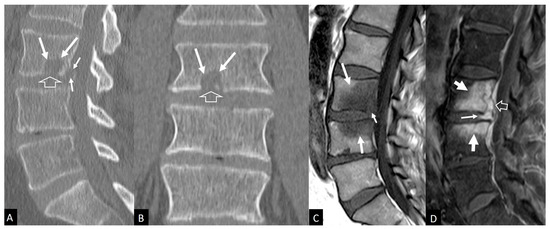

3.4. Imaging